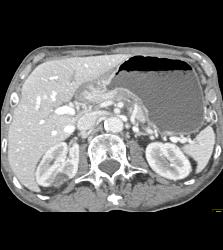

Antral Carcinoma